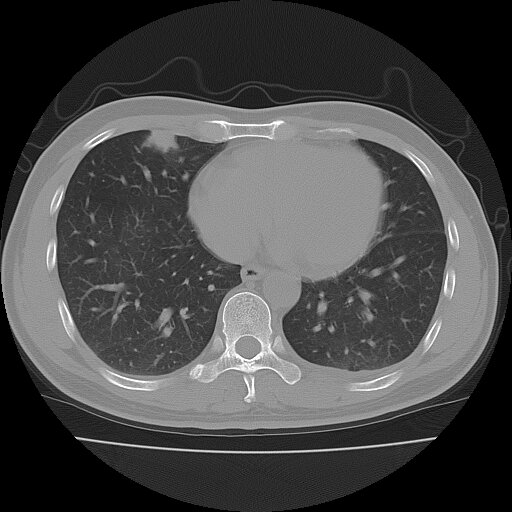

左侧胸痛,无其他病史

考虑肺内炎性肉芽肿,少量胸水。

转移瘤

考虑两肺感染性病变;建议抗炎治疗后复查。

暂考虑两肺感染性病变,左侧少量胸水;建议抗炎治疗后复查

首先考虑双肺感染性病变,左侧少量胸水,见过类似病例,抗炎后都吸收了

右侧胸膜下多发小结节——支持考虑:炎性假瘤!

警惕转移灶